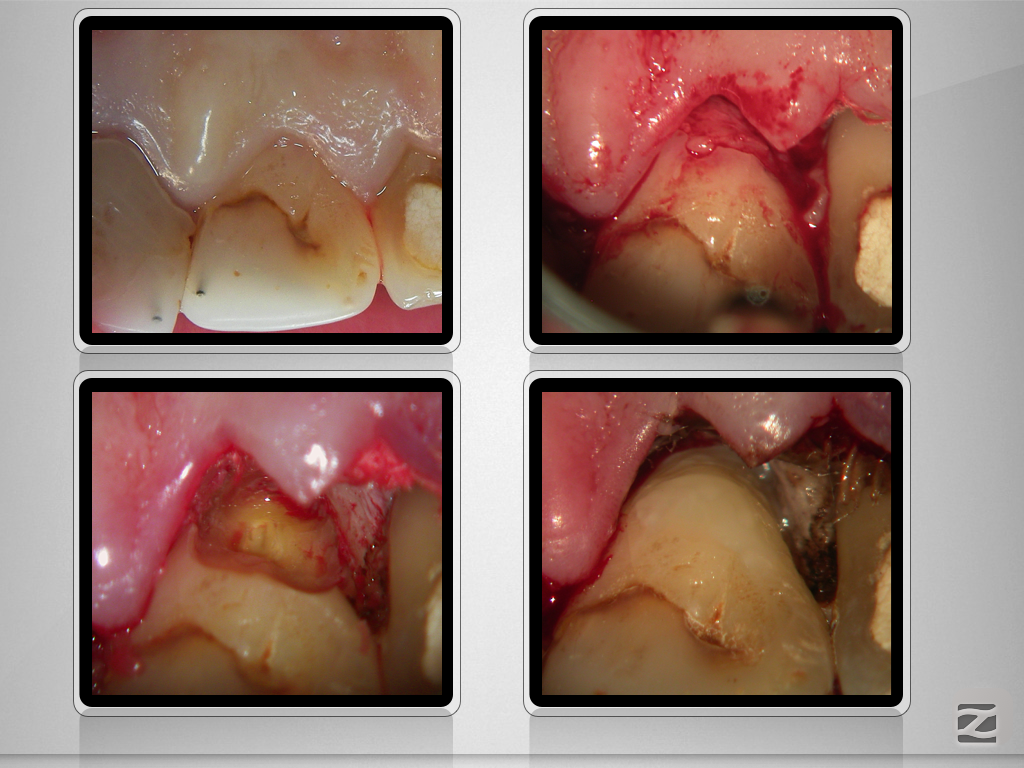

12,11 D.004

Wer hätte es gedacht , …